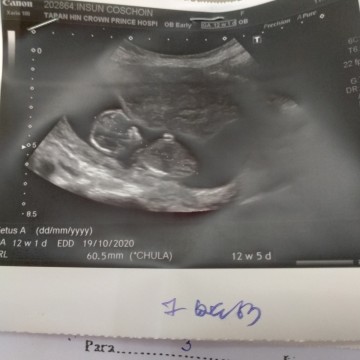

บ้านนี้ตอน12w2dค่ะ

บ้านนี้ตอน12wค่ะ